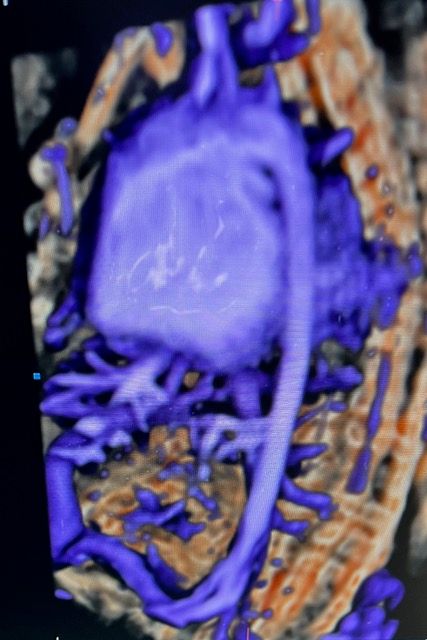

• Ecocardiografia fetale

185 €